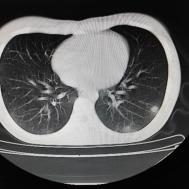

[影像描述]

两肺内及胸膜下多发斑片状高密度影,部分病灶密度较淡,部分实变,边缘可见渗出改变。